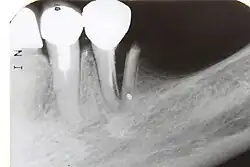

| 7) Root fracture | Mobile or displaced crown segment

Tender tooth that may be bleeding from the gum Tooth may be discoloured (red or grey) |

Fracture line involving the root will be seen as well as the direction | If displaced, reposition tooth and check the position with an x-ray

Flexible splint used to stabilise tooth for at least 4 weeks and then reassess tooth stability Monitor healing for at least 1 year to assess the status of the pulp Root canal treatment will be needed if pulp necrosis develops (this occurs in ~20% of root fractures) |

4 weeks: splint removal, clinical and radiographic examination

6–8 weeks: clinical and radiographic examination 4 months: splint removal in cervical third fractures, clinical and radiographic examination 6 months: clinical and radiographic examination 1 year: clinical and radiographic examination 5 years: clinical and radiographic examination |